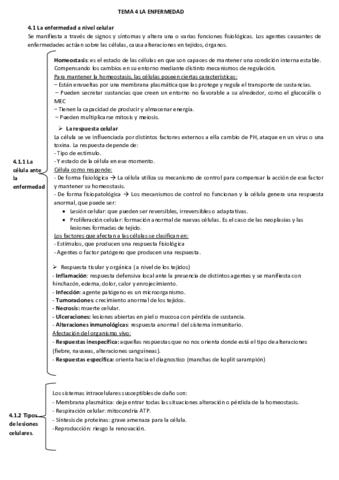

He publicado nuevos apuntes de Fisiopatología general: Tema-4-La-enfermedad.pdf